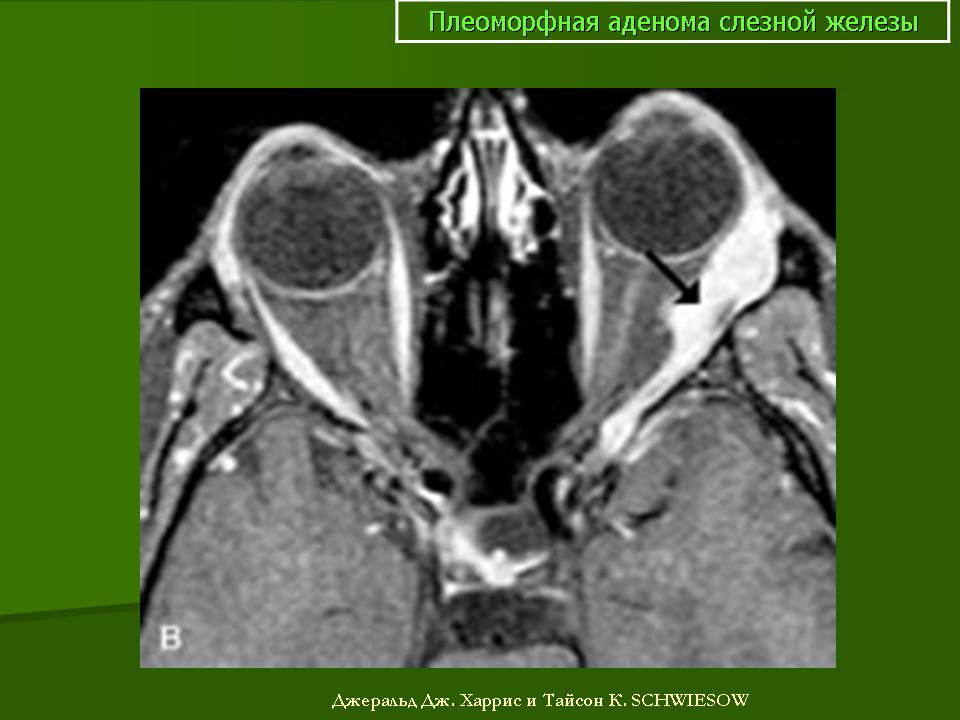

При рентгенографии выявляют увеличение полости орбиты вследствие истончения и смещения кверху и кнаружи ее стенки в области слезной ямки. Ультразвуковое сканирование позволяет определить тень плотной опухоли, окруженной капсулой, и деформацию глаза. При компьютерной томографии опухоль визуализируется более четко, можно проследить целость капсулы, распространенность опухоли в орбите, состояние ее прилежащих костных стенок. Лечение только хирургическое. Прогноз для жизни и зрения в большинстве случаев благоприятный, но пациента следует предупредить о возможности рецидива, который может возникнуть через 3—45 лет. Приблизительно у 57 % больных при первом же рецидиве обнаруживают элементы озлокачествления. Опасность злокачественного перерождения плеоморфной аденомы возрастает по мере увеличения периода ремиссии.